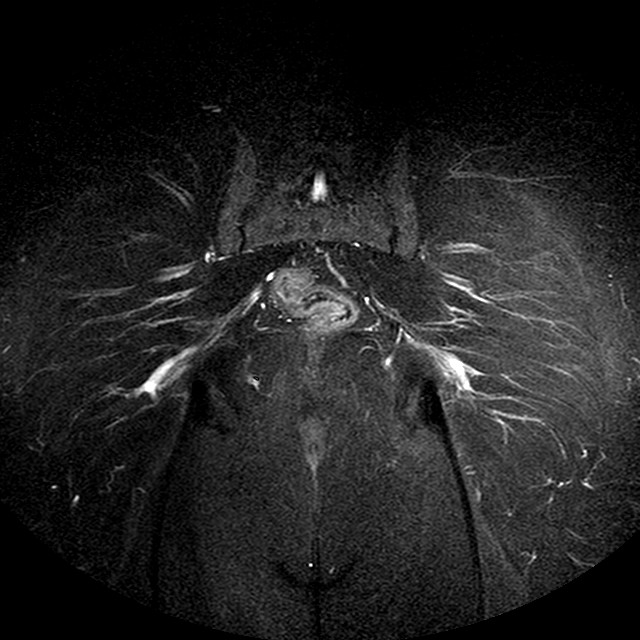

STIR

Evidenti e simmetriche alterazioni osteofitosiche in regione coxo femorale con riduzione delle rime articolari. Degenerazione completa del cercine glenoideo. Non attuali segni di versamento articolare. Non segni di edema osseo che escludono attuale algodistrofia od osteonecrosi. Lieve e simmetrica riduzione del trofismo della muscolatura glutea.